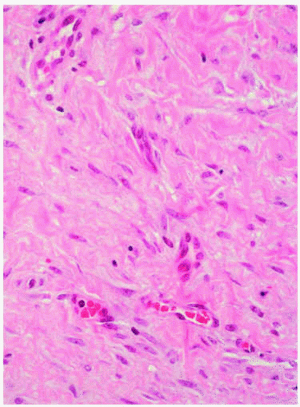

El estudio histológico de tres de estas lesiones mostró en las tres el mismo patrón consistente en una epidermis hiperplásica y una proliferación homogénea de células fusiformes en la dermis profunda que formaba pequeños fascículos con tendencia a disponerse de forma paralela a la superficie cutánea (fig. 4). A gran aumento las células mostraban un citoplasma eosinófilo y núcleos elongados (fig. 5). No se evidenciaban atipias ni mitosis, ni tampoco infiltración profunda del tejido celular subcutáneo.

Fig. 5.--Detalle de las células fusiformes de citoplasma eosinófilo y núcleo elongado sin atipias ni mitosis dispuestas en haces entre-mezclados con colágeno. (Hematoxilina-eosina, x40.)